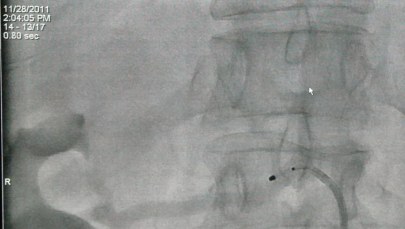

Sam zabieg nosi nazwę denerwacji tętnic nerkowych. Umożliwia on skuteczne obniżeniu ciśnienia tętniczego. Kardiolog wprowadza cewnik do tętnicy nerkowej i za pomocą impulsów elektrycznych moduluje układ unerwienia nerki. Dzięki temu zabiegowi układ nerwowy przesterowuje układ krążenia tak, że spada ciśnienie tętnicze krwi o 10-20 milimetrów słupa rtęci.